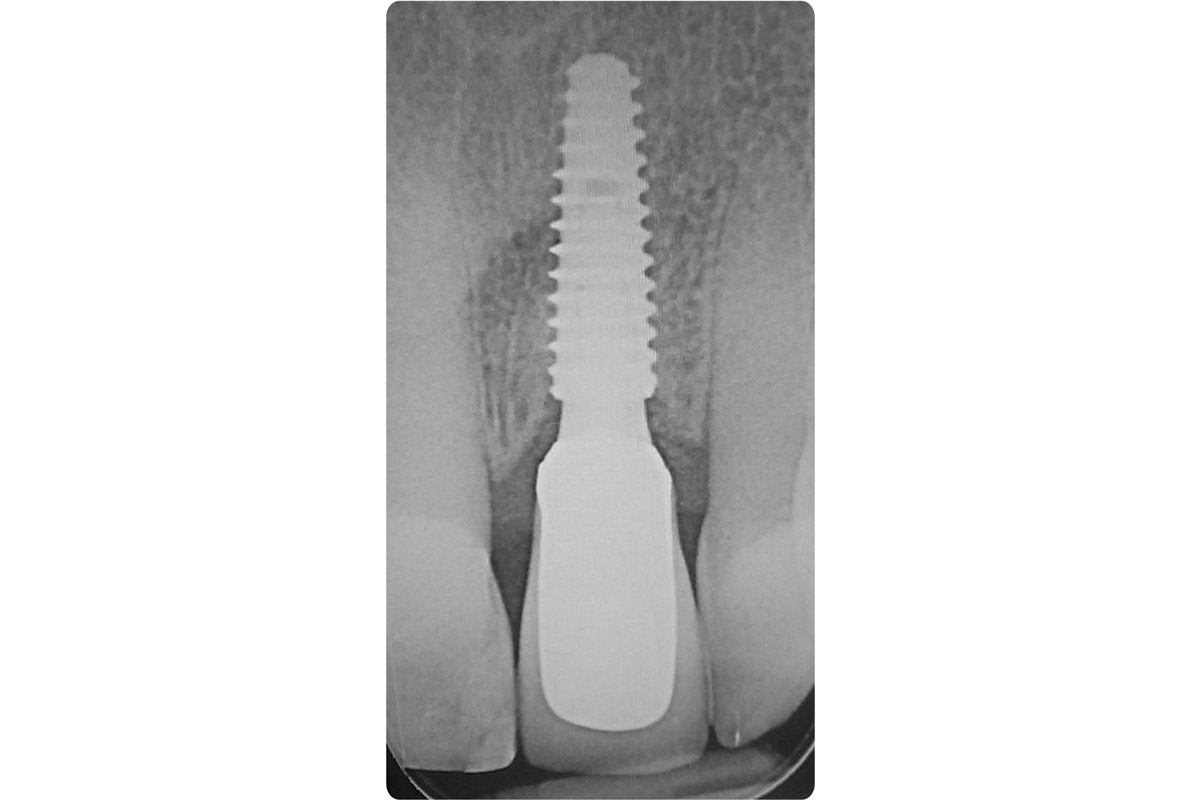

17/18 - X-ray shows good seating of dental implantTooth extraction and socket sealing with mucoderm® - Dr. A. Rossi

18/18 - X-ray with final prosthetic restorationTooth extraction and socket sealing with mucoderm® - Dr. A. Rossi